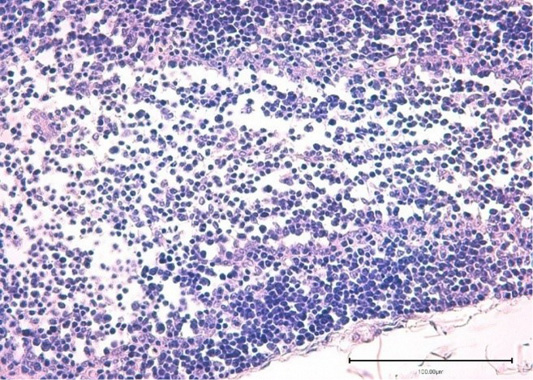

Thymus of broiler chickens in the control group. Stained with hematoxylin and eosin.